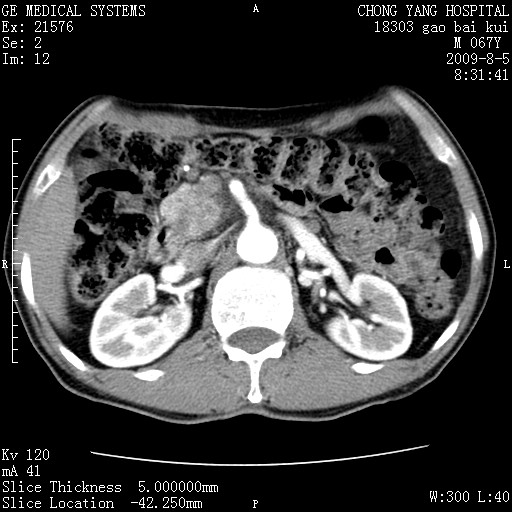

这个也过了,考虑胰腺钩突癌或壶腹癌,不除外胰管粘液乳头瘤伴胰管扩张,肝内胆管积气.

1)考虑胰头癌或壶腹癌并胰管扩张。2)肝外胆管扩张、积气,胆囊影未见;考虑术后改变。3)胃壁增厚?建议必要时行胃镜检查。

考虑胰头癌并十二指肠受侵。